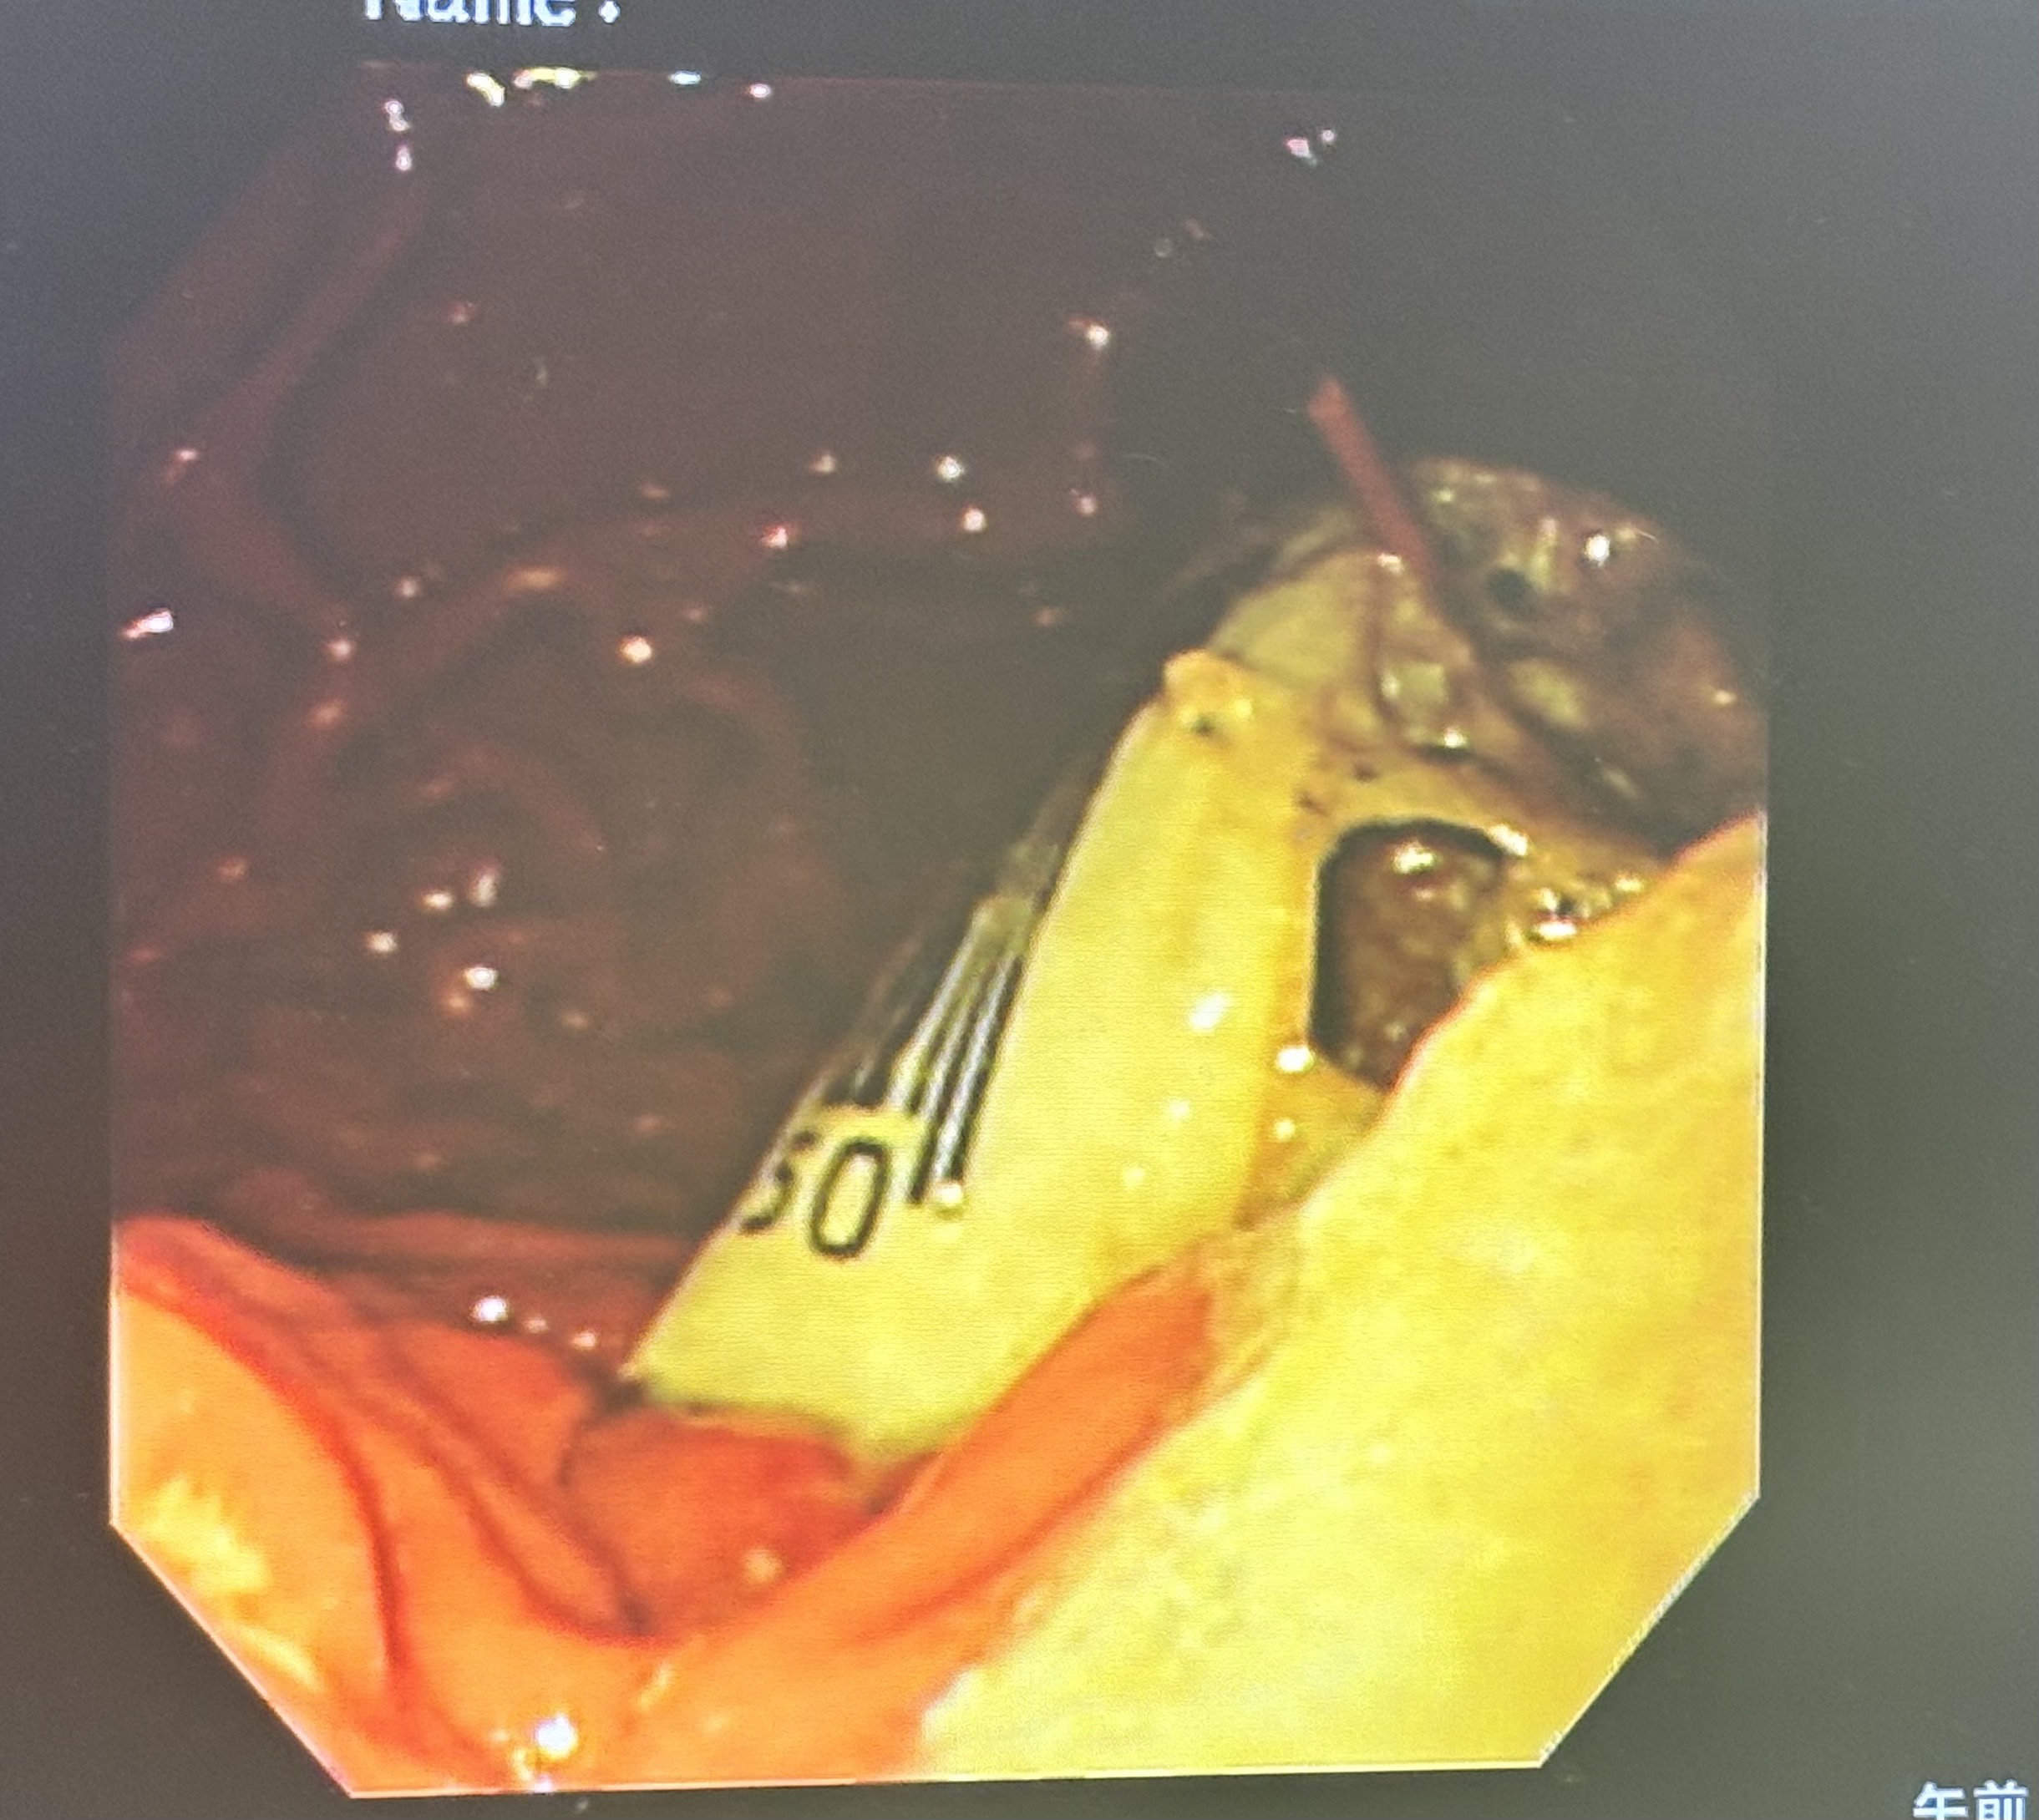

📹 内視鏡検査の様子

胃の中を内視鏡で確認すると、

バーコードのように見える異物がはっきり確認できました。

鉗子を使って、

胃の中からぬいぐるみを無事に摘出できました。

ぬいぐるみ以外にも異物があったので一緒に摘出しました。